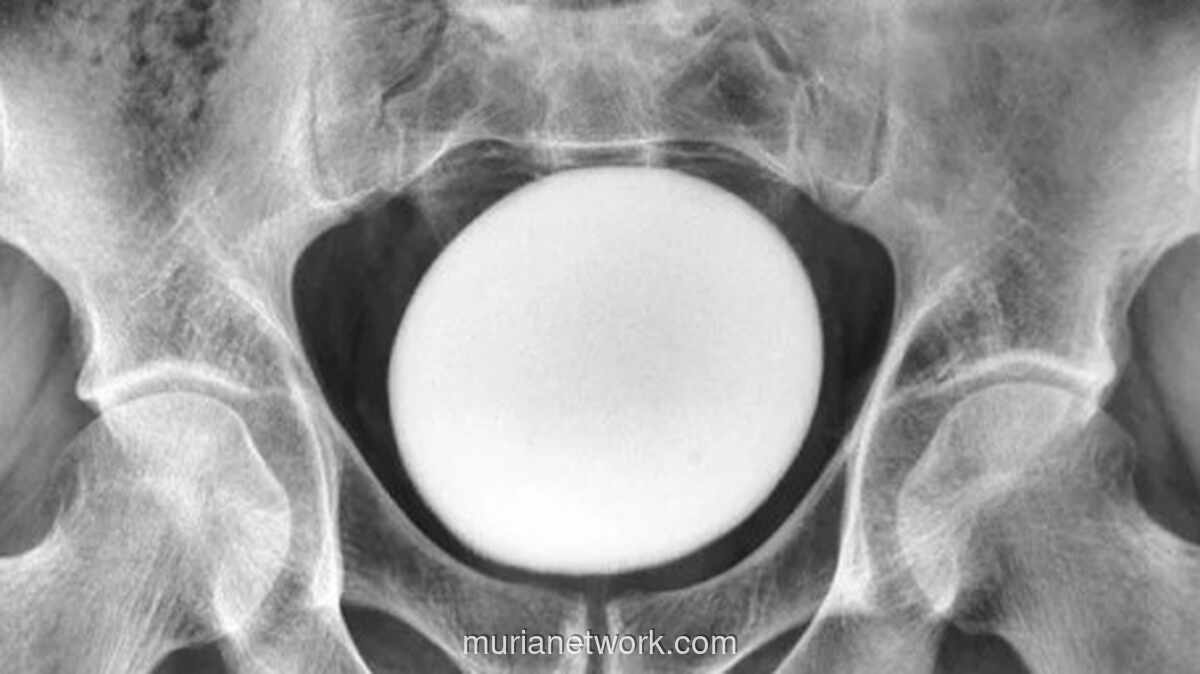

Penasaran, tim medis lalu melakukan USG. Hasilnya mencengangkan: ada benda berbentuk mirip telur raksasa bersarang di kandung kemih, dengan diameter sekitar 11 sentimeter. Temuan ini kemudian dicatat dalam sebuah laporan kasus di NCBI.

Dalam kasus pria Iran ini, untungnya batu itu belum menyumbat saluran kemihnya. Tapi karena ukurannya yang ekstrem, dokter memutuskan untuk mengangkatnya lewat prosedur bedah yang disebut sistolitotomi. Operasinya pun tidak biasa; sayatan harus diperlebar hingga ke bagian belakang kandung kemih untuk mengeluarkan benda asing tersebut.

Dan hasilnya? Sebuah batu dengan berat 826 gram akhirnya berhasil dikeluarkan. Panjangnya sekitar 13 sentimeter, lebar 10 sentimeter, dan tinggi 8 sentimeter seukuran buah alpukat besar.